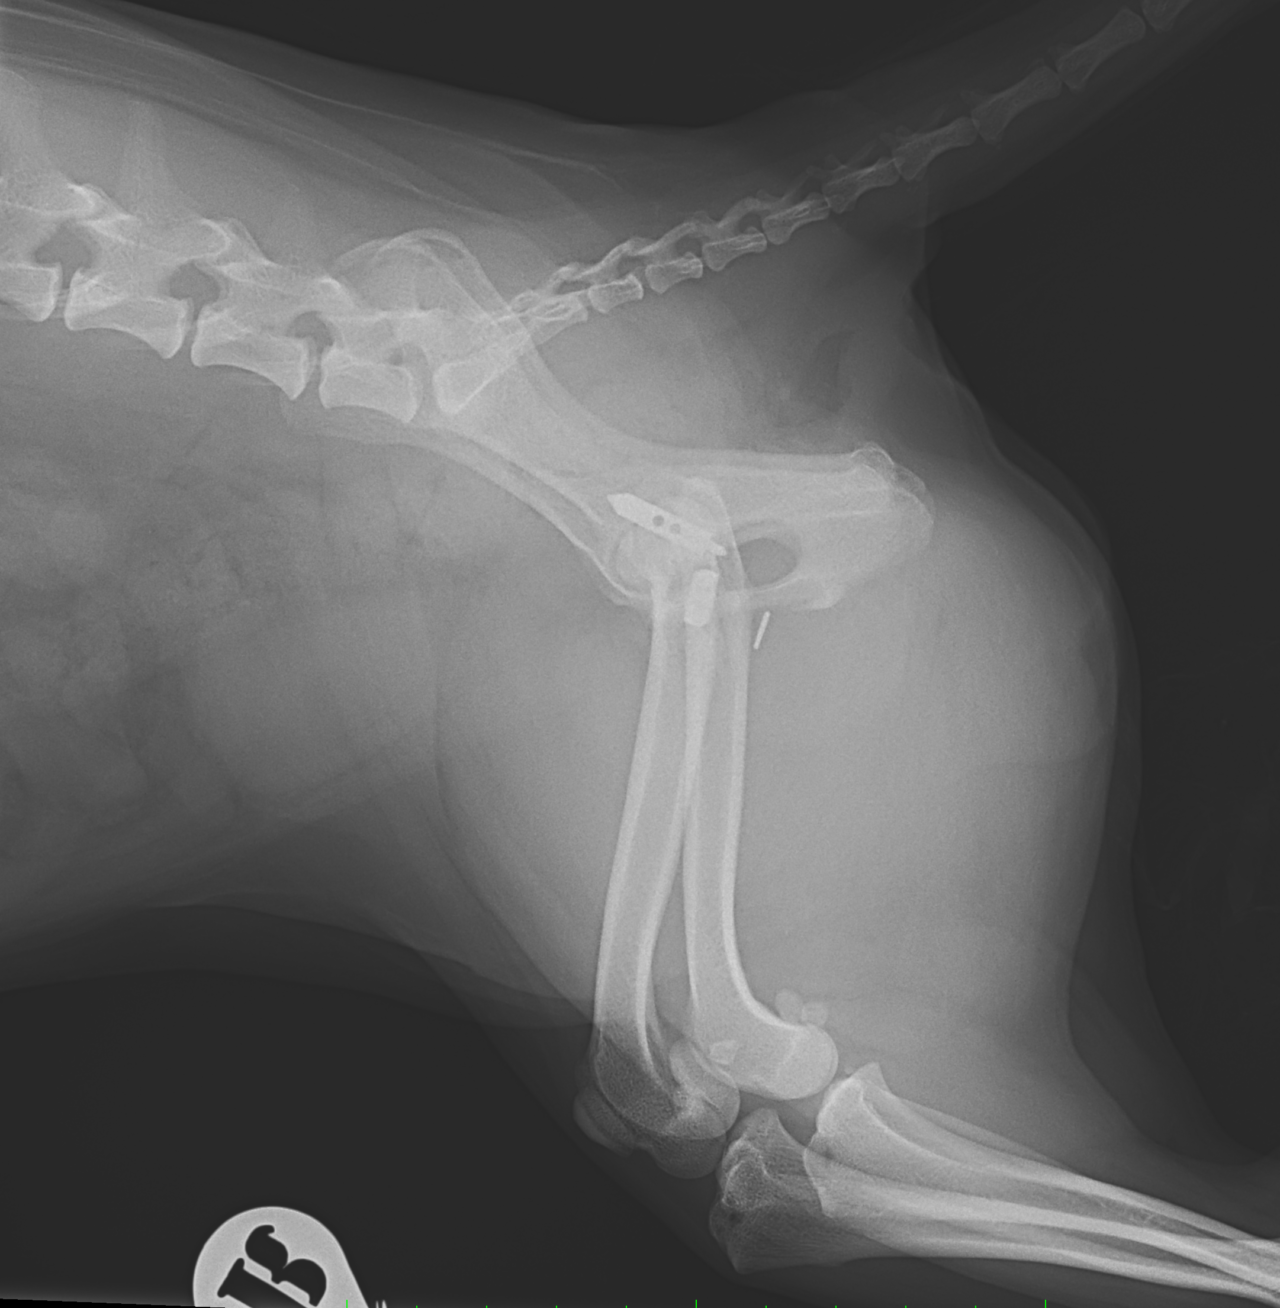

股関節脱臼に対するBUSTOR #67

輪禍外傷による股関節脱臼の患者さんに対してBullet–Shaped Toggle Rod (BUSTOR)で整復を行いました。本症例は恥骨の骨折も併発していたため、CTで寛骨臼の評価も実施しました。低侵襲かつ短時間で整復が可能です。しばらくは安静が必要です。